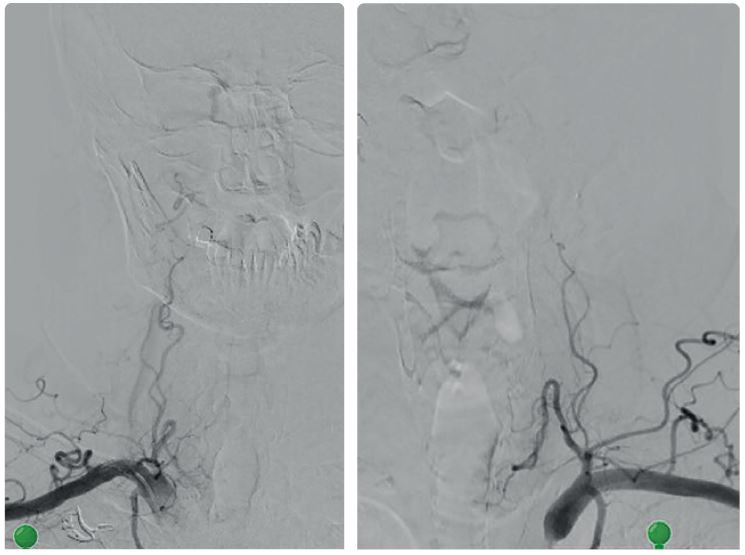

Na zobrazení MR DW (MR obraz s difuzním vážením) byly patrné čerstvé ischemické změny v dolní části levé mozečkové hemisféry v teritoriu PICA (arteria cerebelli inferior posterior) vlevo, a dále v bazi levého brachium pontis. Drobné změny jsou i v teritoriu horní mozečkové tepny vlevo a drobný okrsek restrikce MR DW v dolním okraji pravé mozečkové hemisféry v teritoriu PICA vpravo (obr. 1). Na CTA (výpočetní tomografie – angiografie) a DSA (digitální subtrakční angiografie) byl patrný uzávěr odstupu obou vertebrálních arterií (obr. 2). Zadní mozkové řečiště, tzn. bazilární tepna (BA), PCA a distální části vertebrálních tepen, se plnilo retrográdně cestou zadních komunikant (obr. 3). Retrográdní tok v levé a. vertebralis dosahoval až do extrakraniálního úseku V3 v oblasti oblouku prvního krčního obratle C1 (obr. 4). Nová vyšetřovací modalita QMRA prokázala retrográdní tok v levé zadní komunikantě 30 ml/min a sotva detekovatelný retrográdní tok v bazilární arterii 17 ml/min (obr. 5).

Ze zobrazovacích vyšetření vyplývá, že nemocný má nedostatečnou perfuzi ve VB povodí. Podle studie Veritas jde o „low flow“ pacienta s ročním rizikem opakovaného iktu 22 %.1,2 U těchto pacientů je indikován revaskularizační výkon. Endovaskulární rekanalizace chronického uzávěru vertebrálních tepen nebyla možná, proto jsme se rozhodli provést augmentaci průtoku ve VB povodí pomocí bypassu okcipitální arterie (z povodí a. carotis externa) na horizontální segment vertebrální arterie V3 vlevo. Tímto bypassem jsme plánovali posílit průtok ve vertebrální arterii bypassem z povodí karotidy, obnovit znovu antegrádní tok v bazilární tepně a normalizovat průtok ve VB povodí.